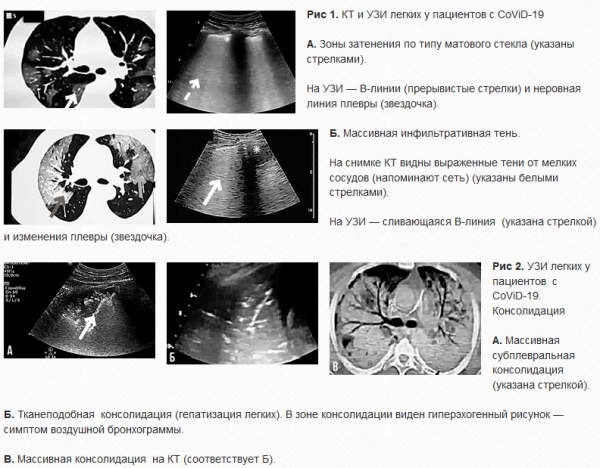

У пациентов с COVID-19 поражение в первую очередь находится в латеральных отделах легочных полей, субплевральной области. Кроме того, могут быть затронуты центральная лобулярная зона и альвеолы. Распределение поражения зависит от силы тяжести. Симптом воздушной бронхограммы на КТ также проявляется, когда на фоне консолидации видны заполненные воздухом бронхи. Ультразвуковая диагностика: основные признаки и механизмы Изменения на УЗИ соответствуют наблюдаемым на КТ. Ультразвуковая картина пневмонии, вызванной CoViD-19, в целом зависит от соотношения воздуха и жидкости в легких. В норме видны плевральная линия и горизонтальные А-линии и отмечается скольжение легкого. При интерстициальном легочном поражении наблюдаются вертикальные гиперэхогенные В-линии, характер которых меняется при ухудшении состояния (рис. 1). Расстояние между ними становится нерегулярным, и при прогрессировании заболевания визуализируются сливающиеся В-линии. Дальнейшая потеря воздушности приводит к формированию консолидаций, чаще всего наблюдаемых в субплевральной области (рис. 2). В-линии отходят от зон консолиации. При выраженной консолидации и тяжелом состоянии пациента легкое приобретает тканеподобную структуру, происходит так называемая гепатизация легкого, на фоне которой может быть виден гиперэхогенный рисунок — симптом легочной бронхограммы. Иногда может наблюдаться плевральный выпот (но он редко встречается при коронавирусной инфекции). Важно оценивать состояние плевральной линии: она становится неровной, появляются неравномерные утолщения, возникает ограничение и затруднение скольжения легкого. Важно, что у одного пациента могут быть практически все эти изменения — одновременно или в разные периоды заболевания: к примеру, в верхней зоне — А-линии, в средней — В-линии и небольшие зоны консолидации, в нижней — плевральный выпот.

Сопоставление УЗИ и КТ Нужно понимать, что УЗИ легких не всегда способно обнаружить патологию, вызванную коронавирусной инфекцией. В частности, этот метод исследования эффективен, если поражение находится в латеральной области. Если в центральной — визуализация не всегда будет информативной. УЗИ удобно тем, что его можно многократно повторять и при этом отслеживать динамику. Для КТ такой подход используется редко (только в случае значимых изменений). Соотношение визуализации и изменений гемодинамики При инфицировании CoViD-19 в первую очередь поражаются эпителиальные клетки легких, а затем интерстиций. На более поздних стадиях происходит повреждение эндотелия и сосудов, могут возникать микроэмболии и геморрагии, даже некрозы в легких. Одновременно ухудшается гемодинамика, растет давление в легочной артерии и возникают поражения правых отделов сердца. Клинические случаи Мужчина, 62 года, госпитализирован 5 февраля с лихорадкой и кашлем. На КТ выявлены множественные двусторонние зоны затенения по типу матового стекла. Подтвержден CoViD-19, вирусная пневмония. Лекарственная терапия (метилпреднизалон 40 мг, иммуноглобулин 5 г внутривенно, антибиотики, арбидол, бафлоксацин) не привела к уменьшению симптомов. Несмотря на ингаляцию кислородом, показатель SpO2 составлял 85 %. 16 февраля пациент переведен в блок интенсивной терапии. Проведена эндотрахеальная интубация из-за выраженной дыхательной недостаточности, центральная венозная катетеризация. Пациент подключен к ИВЛ. Появился респираторный дистресс-синдром. Назначена постоянная терапия фентанилом, пропофолом и кортизоном для седации и анельгезии и мышечной релаксации. По данным эхокардиограммы выявляется выраженное повышение давления в легочной артерии, увеличение правых отделов сердца, сохранение коллабирования нижней полой вены (НПВ), левый желудочек не увеличен. На УЗИ легких — сливающиеся В-линии, ограничение скольжения легкого, плевральный выпот и небольшие зоны консолидации (рис. 3). По данным исследований изменена тактика лечения: положение на животе (прон-позиция) 6 часов каждый день, периодические переворачивания (левая и правая сторона выше), глубокая седация, контроль температуры. Дыхательная функция немного улучшилась. На 28 февраля температура тела держалась на уровне 39,5, объем отделяемой мокроты (желтой вязкой) значитель- но увеличился. Проведена значительная дегидратация. Эхокардиограмма выявила снижение коллабирования НПВ, увеличение правых отделов сердца. При УЗИ наблюдается увеличение объема консолидации и появился симптом легочной бронхограммы. В плане лечения продолжительность положения на животе увеличилась до 16 часов. На УЗИ легких заметны сливающиеся В-линии, зоны консолидации. По данным эхокардиограммы улучшилось соотношение ЛЖ и ПЖ. Прогноз у пациента в целом благоприятный.